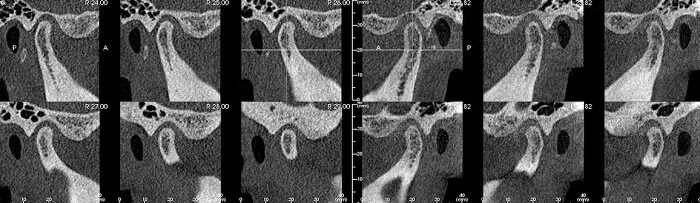

Кт норма височно-нижнечелюстного сустава. Медиальная связка височно-нижнечелюстного сустава. Височно-нижнечелюстной сустав кт анатомия. Протокол описания внчс рентген. Анатомическое строение внчс.

Височно-нижнечелюстной сустав рентген анатомия. Внчс норма. Внчс на кт норма и патология. Внчс норма. Внчс норма.

Височно-нижнечелюстной сустав характеристика. Внчс норма. Дислокация суставного диска внчс. Кт височно-нижнечелюстного сустава. Артрит височно-нижнечелюстного сустава рентген протокол.

Внчс норма. Суставной отросток нижней челюсти анатомия. Кт внчс суставная щель. Внчс норма. Магнитно-резонансная томография внчс.